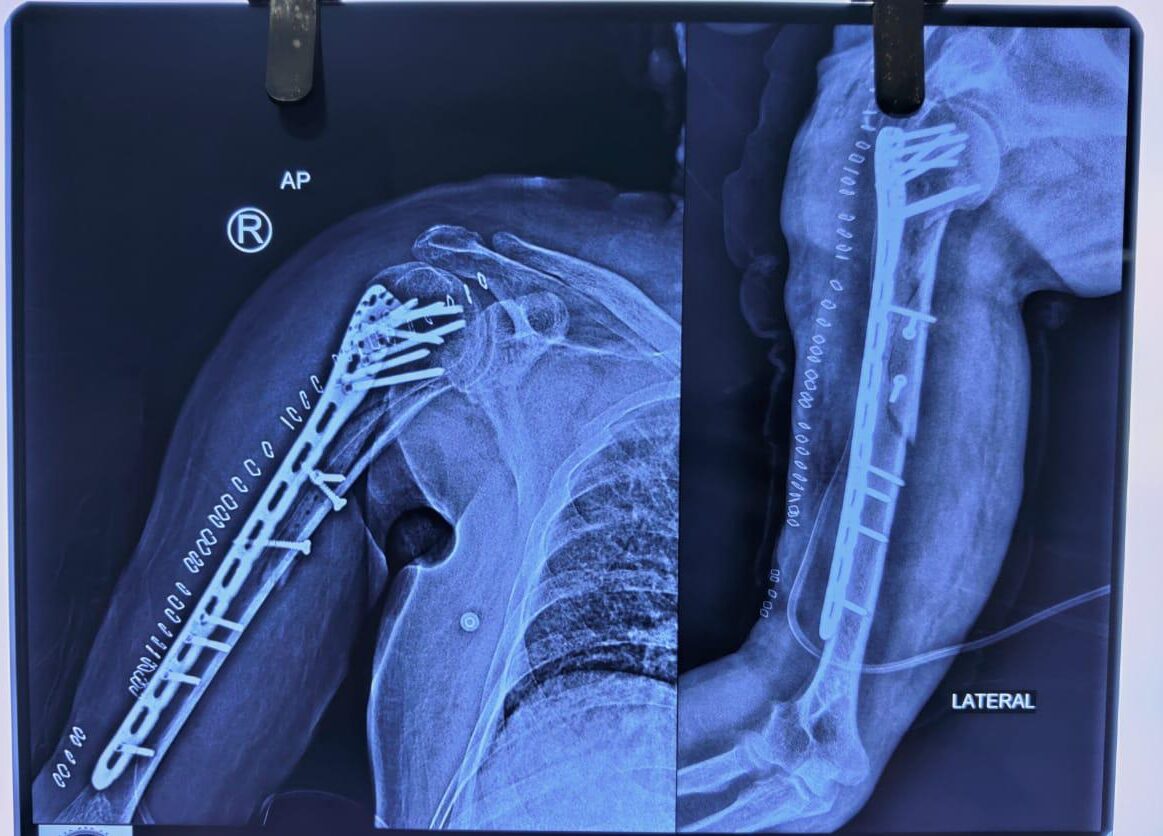

Moments That Mark Meaningful Recovery

Witness real patient transformations at The Ortho Clinic through images that reflect successful treatments and restored mobility.